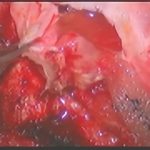

術中写真

摘出 前

摘出 中

摘出 後